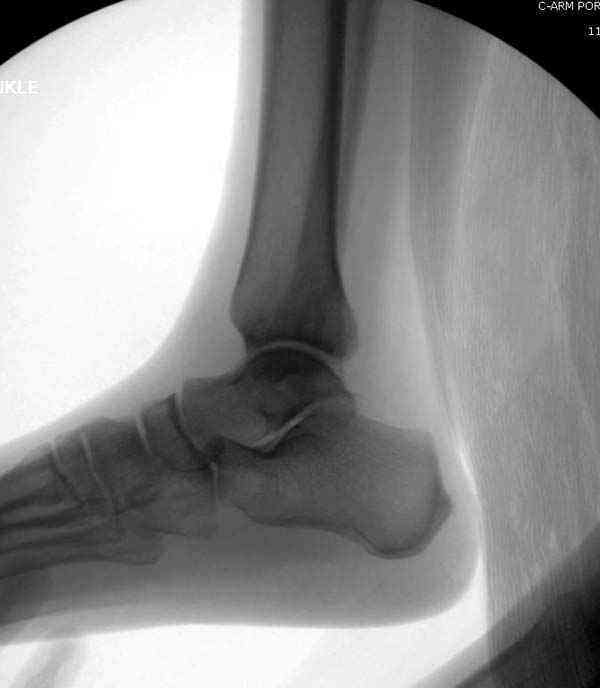

Случай прошлого года:пациентка-молодая ,крупная женщина ,30лет.Травма в начале апреля 2009г-пронационный перелом лодыжек с подвывихом стопы.Ко мне обратилась через 35 дней,прооперирована 22.05.2009г.Внутренняя лодыжка фиксирована по Веберу,наружная реконструктивной пластиной с наложением болта-стяжки.Иммобилизация "сапожок" в течении месяца,затем пригипсовано "стремя".Гипс снят 10.07.2009г

Достаточно быстрое восстановление функции.В октябре 2009г-почувствовала боль,в области рубца над гайкой открылся свищ.На Р-граммах-консолидация переломов и смещение гайки по стяжке.10.11.2009г-конструкции удалены,санация,заживление ран.В настоящее время пациентку ничего не беспокоит.На операции-раскручивание гайки-болталась на конце стяжки.Вопросы:какой механизм раскручивания и что я неправильно сделал?Свои версии:1)в области синдесмоза успела образоваться рубцовая ткань,которая при движении в суставе"пружинила",поскольку голеностопный сустав является спиральным, то и биомеханика подобна кривошипному механизму.2)Реконструктивная пластина не "реконструировалась" по форме лодыжки.Наложил,как есть.То есть подпружинивала сама пластина.Ну,это мои догадки.Что нужно,чтобы избегать впредь таких,пусть и не "страшных"осложнений:Рассверливать через лодыжку область синдесмоза?Ставить шайбу-гровер?Тщательно моделировать пластину?Прилагаю сравнительные снимки-сразу после операции и перед удалением конструкции.

Добрый вечер, коллеги! Хотелось бы увидеть стандартные проекции, прямо, боком и мортиз. Дело скорее всего не в пластине. Стяжка скорее всего не дотянута изначально. Отсюда игра синдесмоза и прорезывание проволоки Вебера. Вообще то стоило бы делать по классике , а именно : Наружная лодыдка - противоскользящая плата по Веберу, над синдесмозом - два позиционных винта ( это "ключи" сустава) внутренняя лодыжка - можно и проволокой, но при адекватной фиксации латерального комплекса.

Раз ,есть желание посмотреть другую проекцию выкладываю-ну лучшего качества нет...